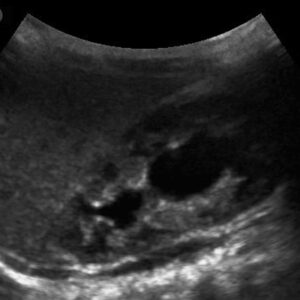

Sonographie (inkl. Duplexsonsographie)

Die Sonographie ist eine der wichtigsten Untersuchungsmethoden in der Kinder-Nephrologie. Sie wird vor allem bei angeborenen Fehlbildungen der Nieren und ableitenden Harnwege, Nierensteinen, Nierenzysten eingesetzt. Mit der farbkodierten Duplexsonographie können zudem die arteriellen und venösen Gefäße der Nieren genau beurteilt werden. Für unsere Untersuchungen nutzen wir modernste Geräte, um präzise Bilder zu erhalten und eine bestmögliche Diagnostik zu gewährleisten.

Ultraschallscreening der Nieren und ableitenden Harnwege bei Neugeborenen

Etwa jedes 100. Neugeborene ist von einer angeborenen Fehlbildung der Nieren oder der ableitenden Harnwege betroffen. Eine frühzeitige Erkennung ist entscheidend, um die Nierenfunktion bestmöglich zu erhalten. Die Untersuchung sollte idealerweise innerhalb der ersten vier Lebensmonate erfolgen, frühestens jedoch am 3. bis 4. Lebenstag, da direkt nach der Geburt die zirkulierende Flüssigkeit im Körper noch zu gering ist, um verlässliche Ergebnisse zu erzielen.